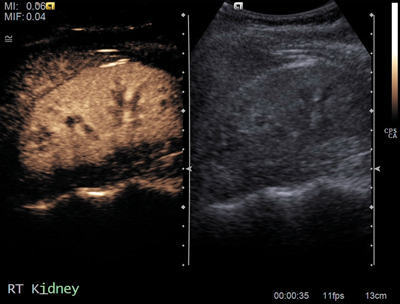

Figure 1a: US demonstrating poorly visualised lower pole.

A horseshoe kidney (Figure 1) is a congenital anomaly in which kidneys are fused by the isthmus at the lower poles. In 90% of cases this is a midline, or symmetrical fusion, but lateral fusion is also a variant. The axis of each renal pelvis remains vertical or in the obliquely lateral plane, and the calyces point posteriorly. The horseshoe kidney lies ectopically with the isthmus located adjacent to the L3 to L4 level. This is due to the inferior mesenteric artery preventing further ascent as it crosses the isthmus. Approximately one third of horseshoe kidneys have a single renal artery to each renal pelvis, whereas the remainder have a variable blood supply [1].

The incidence is 1 in 400 and it is the commonest renal fusion anomaly. There is a male predominance with male to female ratio 2:1. It is often asymptomatic, but patients may present with vague abdominal pain, radiating to the back, ureteral obstruction, or palpable midline abdominal mass. Approximately 50% of horseshoe kidneys have associated vesicoureteral reflux and 30% of patients develop urinary tract infections [1]. Horseshoe kidneys have increased risk of traumatic injury, due to the isthmus lying anteriorly without the protection of the ribs, and it can be split by high impact blunt abdominal trauma [2].

On the plain abdomen film the lower poles of the kidneys are seen medial to the upper poles, in contrast with normal renal anatomy where lower poles are lateral. Ultrasound may reveal the isthmus lying anterior to the spine and contiguous with the lower poles of both kidneys. However due to the positioning of bowel gas centrally, the isthmus may not be clearly viewed and appearances may be of a curved configuration to the kidneys with poorly defined lower poles. In the longitudinal plane the kidneys may appear as an inverted triangular or pyriform shape [3,4]. Contrast enhanced CT will provide the clearest imaging, and helps to define the structural abnormalities of the horseshoe kidney. On CT the following questions can be answered: the degree and site of the fusion, degree of renal malrotation, any associated collecting system abnormalities, and any renal parenchymal changes. CT enables differentiation between normal and fibrous parenchyma within the isthmus, which is almost always functioning tissue.

CT angiography is useful in evaluating arterial anatomy as horseshoe kidneys often have variant arterial supply, including multiple renal arteries, arteries arising from aorta or common, internal or external iliac, or inferior mesenteric arteries [5]. Nuclear medicine imaging can demonstrate fusion with functional parenchymal tissue, and can detect regional loss of function due to obstruction and inflammation [3].